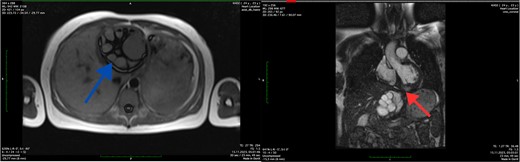

The abdominal ultrasound revealed evidence of cyst formation in the left lobe of the liver, measuring ~10.0 × 8.0 cm in size. Additionally, a bend in the gallbladder neck was observed, accompanied by moderate bile stasis. On the transesophageal echocardiogram, no blood clots were detected in the left atrial appendage or cardiac cavities. The CT scan revealed uniform filling of the left portions of the heart with a contrast agent, indicating an absence of filling defects. Notably, structures within the myocardium near the diaphragm on the posterior lower wall of the left ventricle were identified as round-oval formations with clear contours. These formations exhibited densities ranging from +12 Hounsfield units to +44 Hounsfield units and measured 5.4 × 4.2 × 2.7 cm. Moreover, imaging of the left lobe of the liver depicted a heterogeneous structure attributed to the presence of a cystic formation. This formation displayed a density of up to +17 Hounsfield units and manifested as a round-oval structure with thickened walls. The cyst contained septa and areas of calcification, measuring up to 7.8 × 7.5 cm. Based on the CT scan findings, a diagnosis of echinococcal cyst was established. The presence of echinococcal cysts was noted in both the myocardium of the left ventricle of the heart and in the liver (Fig. 1).

Axial CT scan showing the cystic lesion in the left lobe of the liver (blue arrow) and axial CT scan showing the cystic lesion in the left ventricle (red arrow).